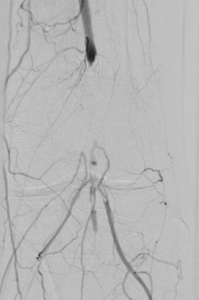

6. Fibrinolyse – medikamentöses Auflösen von Blutgerinnseln

Gefäßverschließende Blutgerinnsel können auch durch Medikamente aufgelöst werden, um den Blutfluss wiederherzustellen. Damit dieses Medikament sicher und effektiv wirken kann, wird es über einen Katheter direkt zum Verschluss gebracht. Das erfolgt über eine langsame mehrstündige Gabe. Zur Verbesserung der Wirkung kann durch Spezialkatheter das Medikament mit Hilfe von Schallwellen in das Blutgerinnsel transportiert werden.